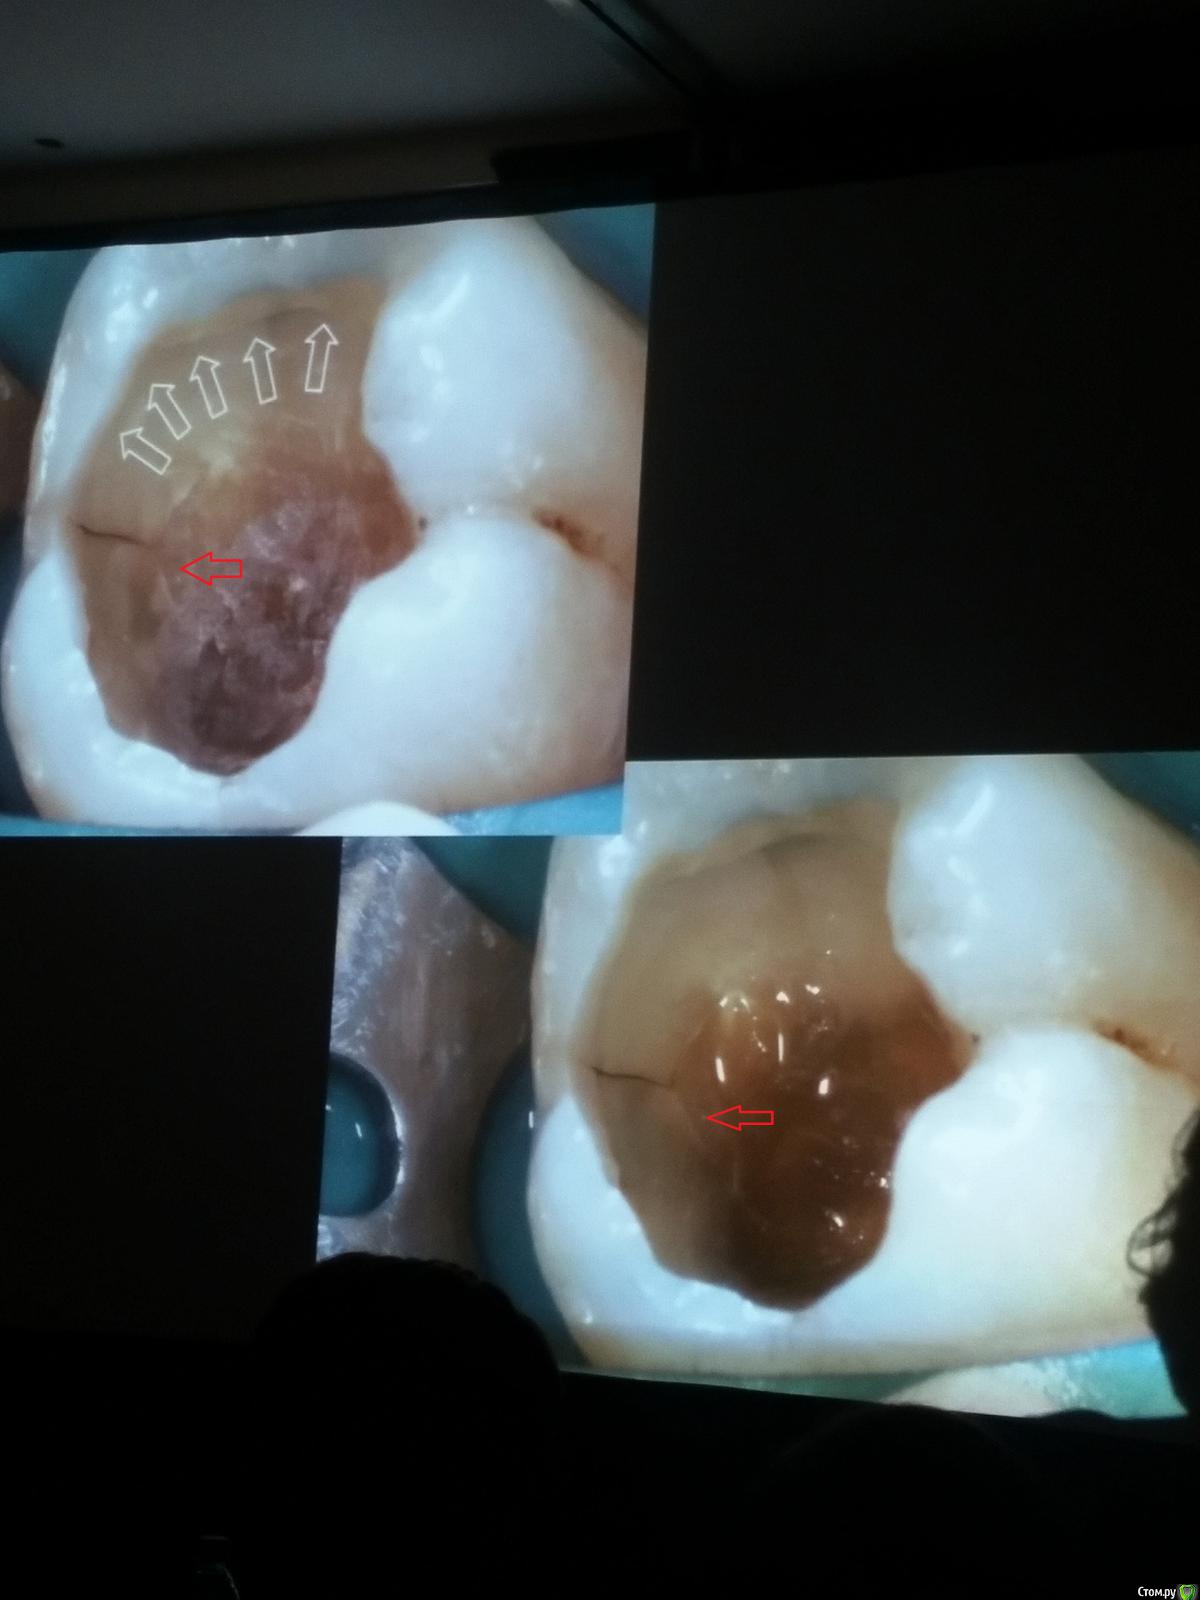

Популярный пост Kolchanov Опубликовано 11 марта, 2017 Популярный пост Поделиться Опубликовано 11 марта, 2017 (изменено) Товарищи, скажу я вам...........Вкратце. Может я где-то что-то и приврал, надеюсь, кто еще был, поправят. Честно говоря немного прибалдел от уровня Доктора. Очень, очень высоко! Приедет еще раз, пойду еще. 1) Фиссуры зондирует острым зондом и выпиливает все дотла. По факту у него уже пломбы, а не герметизация.2) Bite-wing у первичных пациентов всегда.3) Если кариес диагносцирован, то лечить его, пофиг какой он там. Эмали, дентина…4) Препарирует до твердого (или до вскрытия J ). CAD, СID… в топку. Кариес маркером не пользуется, проверяет острым зондом/экскаватором. Вычищает все дотла. Считает, что даже небольшое количество бактерий в дентине под пломбой вызывают хроническое воспаление в пульпе. С его слов у него на контроле где-то 500 вскрытий, не удивительно при таком подходе к очистке.5) Тщательная изоляция. Коффер порвался – меняет. Большое значение герметичности реставрации. под замену6) Критерии обратимости и необратимости.Гистологически, обратимый тот, что без абсцессов в пульпе, но клинически это понять нельзя, только предположить.Здесь был бы обратимый, если бы не удалил. Нет микробов в пульпе. Линия - граница обработки.Покрытие 27 лет назад. Dycal, СИЦ, композит. От дайкала одно воспоминание.7) Вскрылись. Размер перфорации, возраст и прочее не играют роли, важно только состояние пульпы, т.е. диагноз.Примеры перфораций.8) Кровотечение останавливает стерильным ватным шариком. Если останавливается, то покрытие, если нет, то пульпотомия или пульпэктомия.9) Использует гидроокись кальция (порошок), перекрывает Dycal или СИЦ. Потом восстановление Нередко под IRM, потом все убирает (через пару-тройку месяцев) и смотрит, что получилось. Порой приходится повторять! Использует и МТА, его тоже убирает.10) Наблюдение 6мес, 1 год, 2…. Все может провалиться и через месяц и через 24 года.Примеры проваловНиже - 24 года спустя появилась дуля. 11) Неравномерная облитерация полости зуба на RG (после покрытия) – признак текущего хронического воспаления, где-то остались микробы. Рекомендует эндо.12) Мостик который образуется – это не дентин! И одонтобласты не регенерируют и новые не образуются. Что это такое он и сам не знает, но раз это твердые ткани, то и наплевать.Вот фиолетовое это дентинные опилки вмурованные в розовую ткань бог знает кем сформированную.13) Пульпотомия в зубах с несформированной верхушкой и в сформированных, при подозрении на частичное поражение коронковой пульпы. Иссекается стерильным алмазным бором часть пульпы, гидроокись, временная пломба на 90 дней, после повторное раскрытие, оценка результата, восстановление в случае формирования твердых тканей. Гипохлоритом можно мыть, можно не мыть, если мыть, то 0,5-1%.14) В апикальной части пульпа чаще витальна, чем нет.15) Периапикальные поражения возникают по причине поступления токсинов микробов с током крови, а не самих бактерий.16) За апикальные расширения в полностью некротических случаях. Надо механически отодрать биопленку и срезать инфицированный дентин. На ирриганты надежды мало.17) Биопленка на поверхности в 6% случаев.Синенькие пид@расы18) Обработку проводить нежно, краун-даун. Чередовать с H-файлом, чтобы посмотреть докуда распространяется некроз.19) Патенси в витальных кейсах не колоть, сохранять витальную пульпу в констрикции!Формирование еще большего сужения в констрикции за счет сохранения витальной пульпы. Изменено 11 марта, 2017 пользователем Kolchanov 31 Ссылка на комментарий

Популярный пост Kolchanov Опубликовано 12 марта, 2017 Автор Популярный пост Поделиться Опубликовано 12 марта, 2017 Второй день.1) Дезинфекция зуба и раббер дама перед работой. Вначале установка системы, потом протирка тампоном 30% перекиси, потом протирка всего йодинолом. Потом преп, потом повторение и только потом доступ к к/к. Все старые реставрации надо убрать, кариес убрать, противник лечения через коронку.2) Гидроокись на неделю. Замешивает на стерильном физрастворе. При необходимости повторяет. Т.е. в случае сохранения свища, симптоматики, экссудации, запаха. Если свищ не исчезает после трех смен временных вложений, то хирургия.3) Пломбирует латеральной компакцией. Лучше контроль длины обтурации.4) Высушивание канала стерильными штифтами, на рабочую длину минус 1мм. После высушивания штифт оставляется на 60с. в канале и должен выйти сухим.5) Определение рабочей длины. Витальные случаи. АЛ должен три раза дать одну и ту же картинку в определенной точке + проверка RG. Девитальные случаи. На АЛ полагаться сложно, т.к. из-за наличия резорбции констрикции может врать, больше ориентируется на RG.6) Использует ЦОЭ силеры. Резорбируются при незначительном выведении. Резорбируются в канале, позволяя закрыть апекс цементоподобной тканью. Вот так вот.Случаи исчезновения силера, как за пределами канала так и в канале7) Выведение материала (не важно какого) в большом объеме способно вызвать защитную реакцию тканей. Которая должна пройти спустя некоторое время. (иногда это будет 25 лет J Случай 1ый. Студенты наломали инструментов. Периодонтит на RG через год. Резекция и гистология. Бактерий не обнаружил. Да, маленькое замечание. Каждый препарат дает 500-600 срезов. И ищет он на всех. Объем работы, конечно….Случай 2й. Его собственный. Периапикальное поражение, обнаруженное на реколле через 10 лет зажило еще через 15.8) «Функционирующий зуб» считает результатом неприемлемым. Осталась инфекция с которой надо что-то делать. То, что бактерий можно замуровать в дентинных трубочках и под пломбировочным материалом, считает неправильным. Продукты метаболизма один фиг будут просачиваться и могут поддерживать реакцию воспалительную.Случай. Синее – маленькая кучка микробов, предположительно, препятствовавших заживлению очага.9) Биопленка на поверхности корня может принимать вид кальцификатов (камней) и тут уже только хирургия в помощь. При длительном существовании свищевого хода, например.Черное - это камни вокруг апикального отверстия. И гистология их с кучей синих микробов.Здесь камни на фуркации и отсутствие заживления и свищ даже после ретроградной обработки и пломбировки.А здесь вообще чертова уйма камней. И зацените разветвление канала в этом боковом резце (последнее фото препарата). 10) Реваскуляризация.В некротических случаях дентина не образуется, т.к. одонтобластов нет и не будет новых. Образуется та самая бог знает какая ткань, которая даже и с корнем не связана может быть. Суть здоровый дентикль-петрификат. А в витальных это не реваскуляризация, а обычное формирование корня. Так что нечего тут.11) Трещины дентина.Советует расшивать, братья и сестры. Без фанатизма, если нет симптоматики, но, по возможности максимально. Если есть симптоматика, то там уже по обстоятельствам. Чертова уйма микробов там и ползет, ползет к пульпе. Надеюсь, что еще раз этот замечательный Доктор приедет. Схожу с удовольствием. 2 23 Ссылка на комментарий